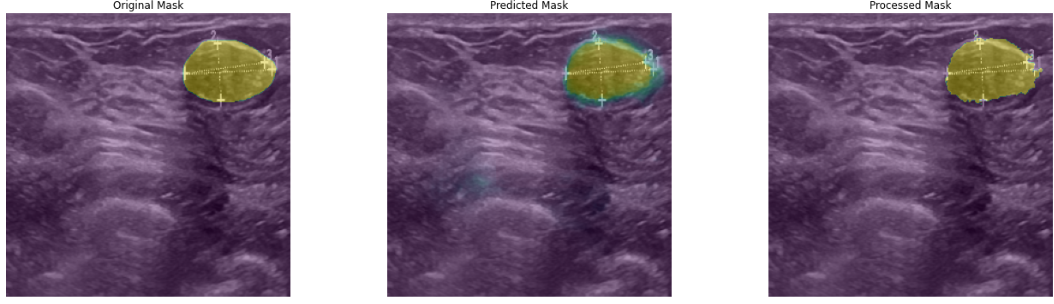

The Segmentation Model for Breast Cancer Ultrasound Image based on Attention U-Net

The segmentation of ultrasound image for breast cancer is an important task in the field of biomedical research. The traditional U-Net model, with its simple structure and remarkable performance, this approach has found extensive application in the segmentation of medical images. However, U-Net tends to be affected by background noise when handling images with complex backgrounds or blurry boundaries, which may impact the segmentation accuracy. To address this issue, the Attention U-Net model incorporates an attention mechanism, enabling the model to selectively focus on critical target areas within the image, thereby improving segmentation accuracy. This paper further optimizes the Attention U-Net architecture by increasing the depth of both the encoder and decoder sections, enhancing the model's capacity for feature extraction and image reconstruction. Consequently, both the accuracy and robustness of segmentation are enhanced. The experimental findings indicate that the proposed modified Attention U-Net model significantly outperforms traditional methods in breast ultrasound image segmentation tasks. It effectively handles various types of breast images, particularly those with complex backgrounds, blurred targets, or small sizes, maintaining high segmentation accuracy. This study offers an effective solution for the automated segmentation of breast ultrasound images, with substantial implications for enhancing both the automation and diagnostic efficiency in medical image analysis.